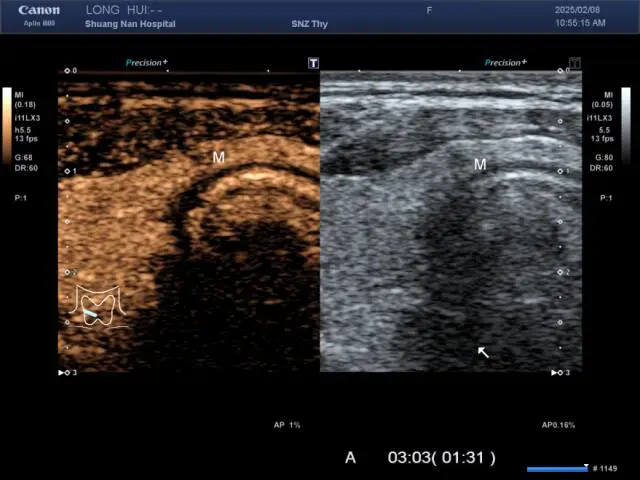

从“小米粒”到“微小癌”,超声造影这位“判官”是如何断案的?刘先生的“小米粒”在超声造影过程中,呈现以下变化:

显影慢半拍:坏疙瘩22秒才“磨蹭亮”,颜色也很暗,正常组织 22 秒就“亮灯”。

内部有黑点:25秒时出现“针尖小黑洞”,可能是细胞坏死或钙化。

退场特别快:2分钟后,周围还亮着,它先“熄灯”,典型坏疙瘩特征。